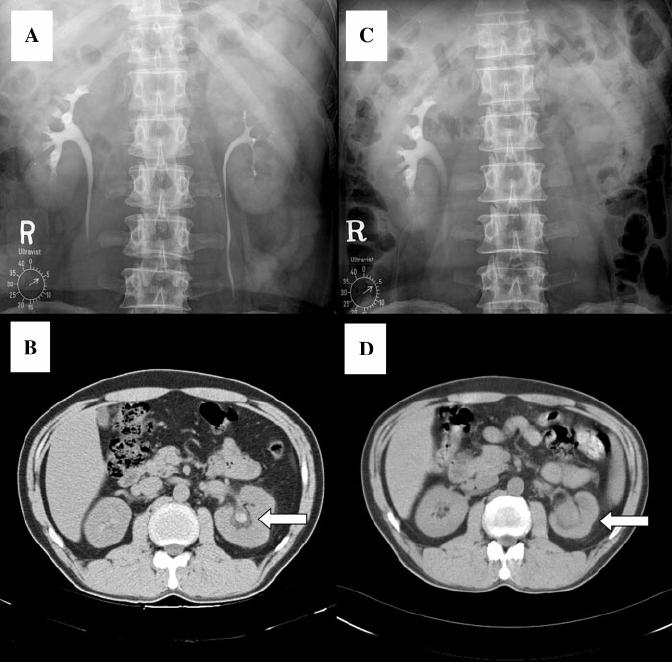

This case is not of trauma, Spont haematoma renal IGA but it does show non-opacification of the kidney on an IVP as an example.

https://www.researchgate.net/publication/6852479_Spontaneous_renal_pelvic_haematoma_mimicking_cancer_in_IgA_nephropathy/download